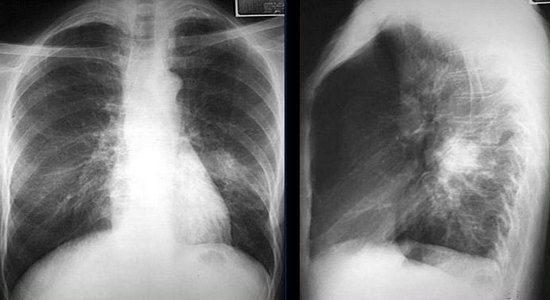

- Рентгенологическое исследование. Рентгенограмма легких в двух проекциях выявляет множество сливающихся теней размером до 2 сантиметров (фото).

Очаговая пневмония на рентгенограмме

- рентгенография грудины;

Рентгенограмма при очаговой пневмонии